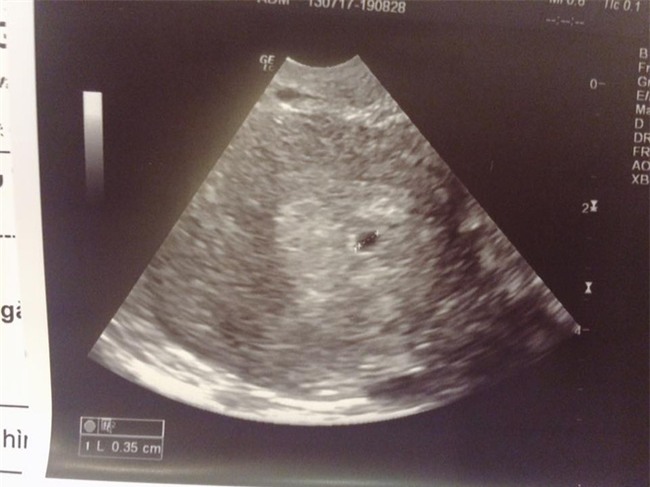

"Con của em được 5 tuần rồi. Em có nói chuyện với mẹ (vì bọn em có bé trước khi cưới) mà mẹ em thì rất tin vào bói toán. Mặc dù biết người yêu hơn em 11 tuổi (sinh năm 83) nhưng nhất định mẹ bắt em phải sau 27 mới được lấy và 28 mới được có em bé, vì bà ngoại em đi xem bói ở đâu đó nói nếu em lấy chồng trước 27 tuổi thì đến năm 32 tuổi vợ chồng em sẽ ly hôn.

Sau khi em báo tin có bầu, mẹ em hỏi han về anh người yêu, rồi hỏi sẽ sống như thế nào. Em nói lương anh ấy ổn định (vì là người nước ngoài làm ở Việt Nam nên lương tháng cũng 60 triệu chưa kể tiền trợ cấp ăn) mẹ không cần lo lắng quá. Vậy mà mẹ em vẫn nói "60 triệu thì là cái gì". Em vẫn cảm thấy sợ mẹ em sau câu nói "mới có 5 tuần bỏ cũng được chứ sao"... Em hận bản thân vì không thể làm gì hơn...